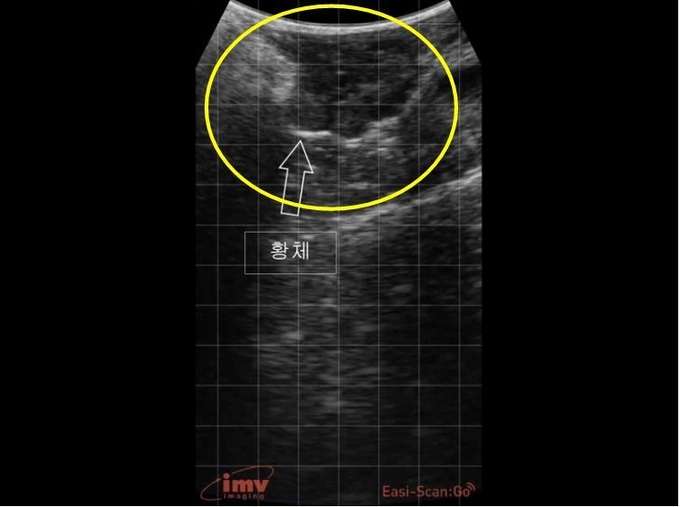

2. 직장초음파 영상으로 보는 모돈의 번식기관의 정상 사진과 대비되는 질병 초음파 영상

모돈의 번식질환은 번식과 관련한 기관별로 주요 번식질환을 구분할 수 있다. 기관별로 자주 발생하는 번식기관 문제와 진단된 초음파 영상을 보도록 하자.

①난소